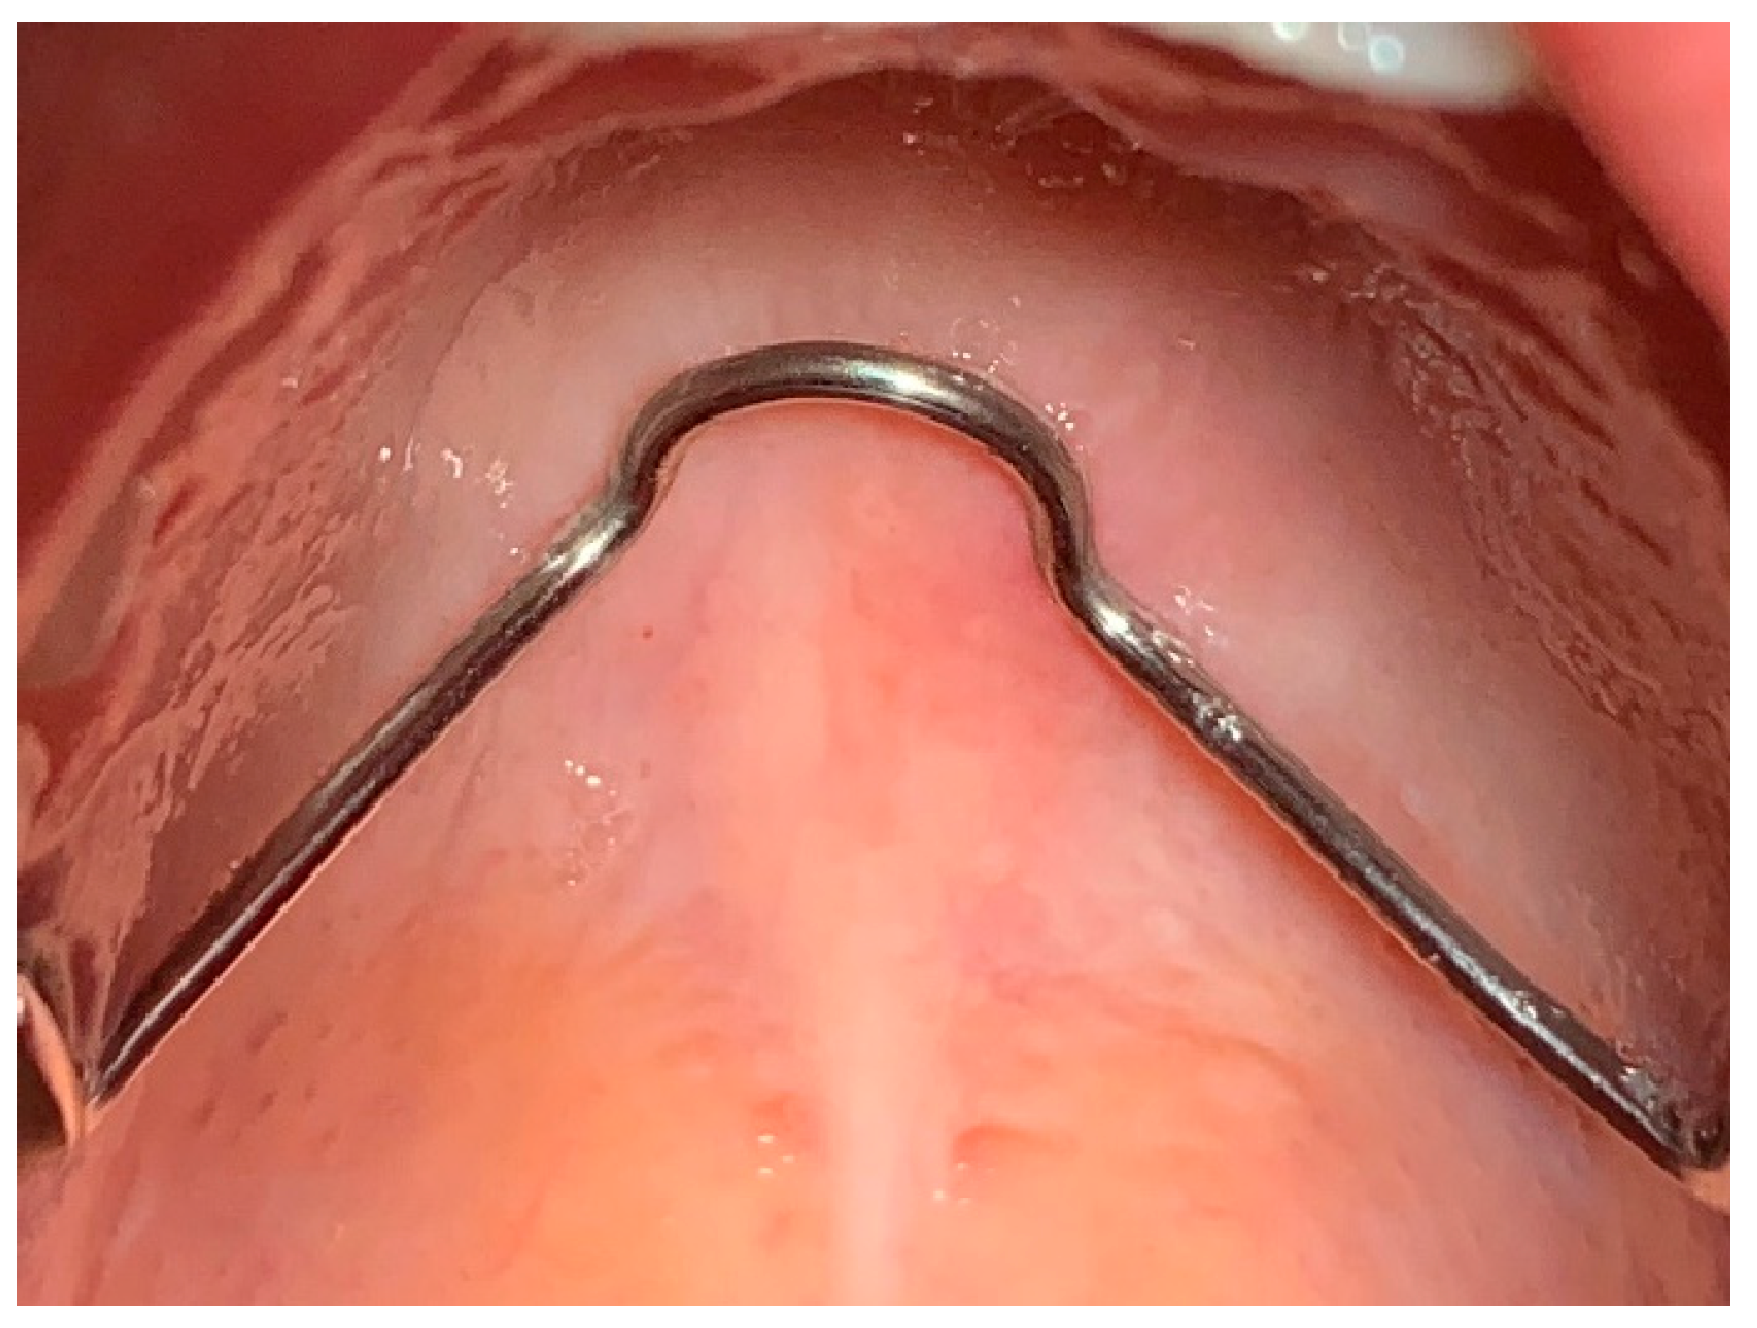

Traditionally, the Herbst device involves taking impressions of patients with permanent dentition with 4 bands for each arch, respectively first molars and first permanent premolars. The technical laboratory proceeds to solidify the bands by including the second premolar with shaped buccal and palatal bars in the archorage unit. Therefore the premolars and the molar of the same hemi- arch work as a single anchorage unit. The right unit and the left unit of the same arch are connected and mutually stabilized by wire elements of appropriate diameter: for the upper arch there is a trans-palatal bar welded onto the bands of the sixths and distanced from the soft tissues to avoid mucous decubitus on the palate; for the lower arch there is a lingual arch welded onto the first premolar which touches the tracks of the lower incisors. These wire elements serve to increase the stability of the anchoring units and reduce the effects of unwanted muscle forces (

Figure 1A). In our opinion, this structure is the most solid, least subject to breakage, most effective in managing anchorage and best performing since it leaves the dental cusps of the teeth with bands exposed. Indeed this allows the dental gear when you bring your teeth to contact.